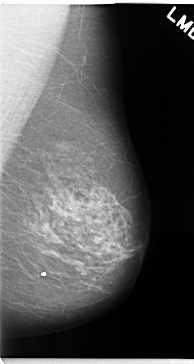

C_0128_1.LEFT_MLO

LEFT_MLO LINES 4720 PIXELS_PER_LINE 2512 BITS_PER_PIXEL 12 RESOLUTION 50 NON_OVERLAY